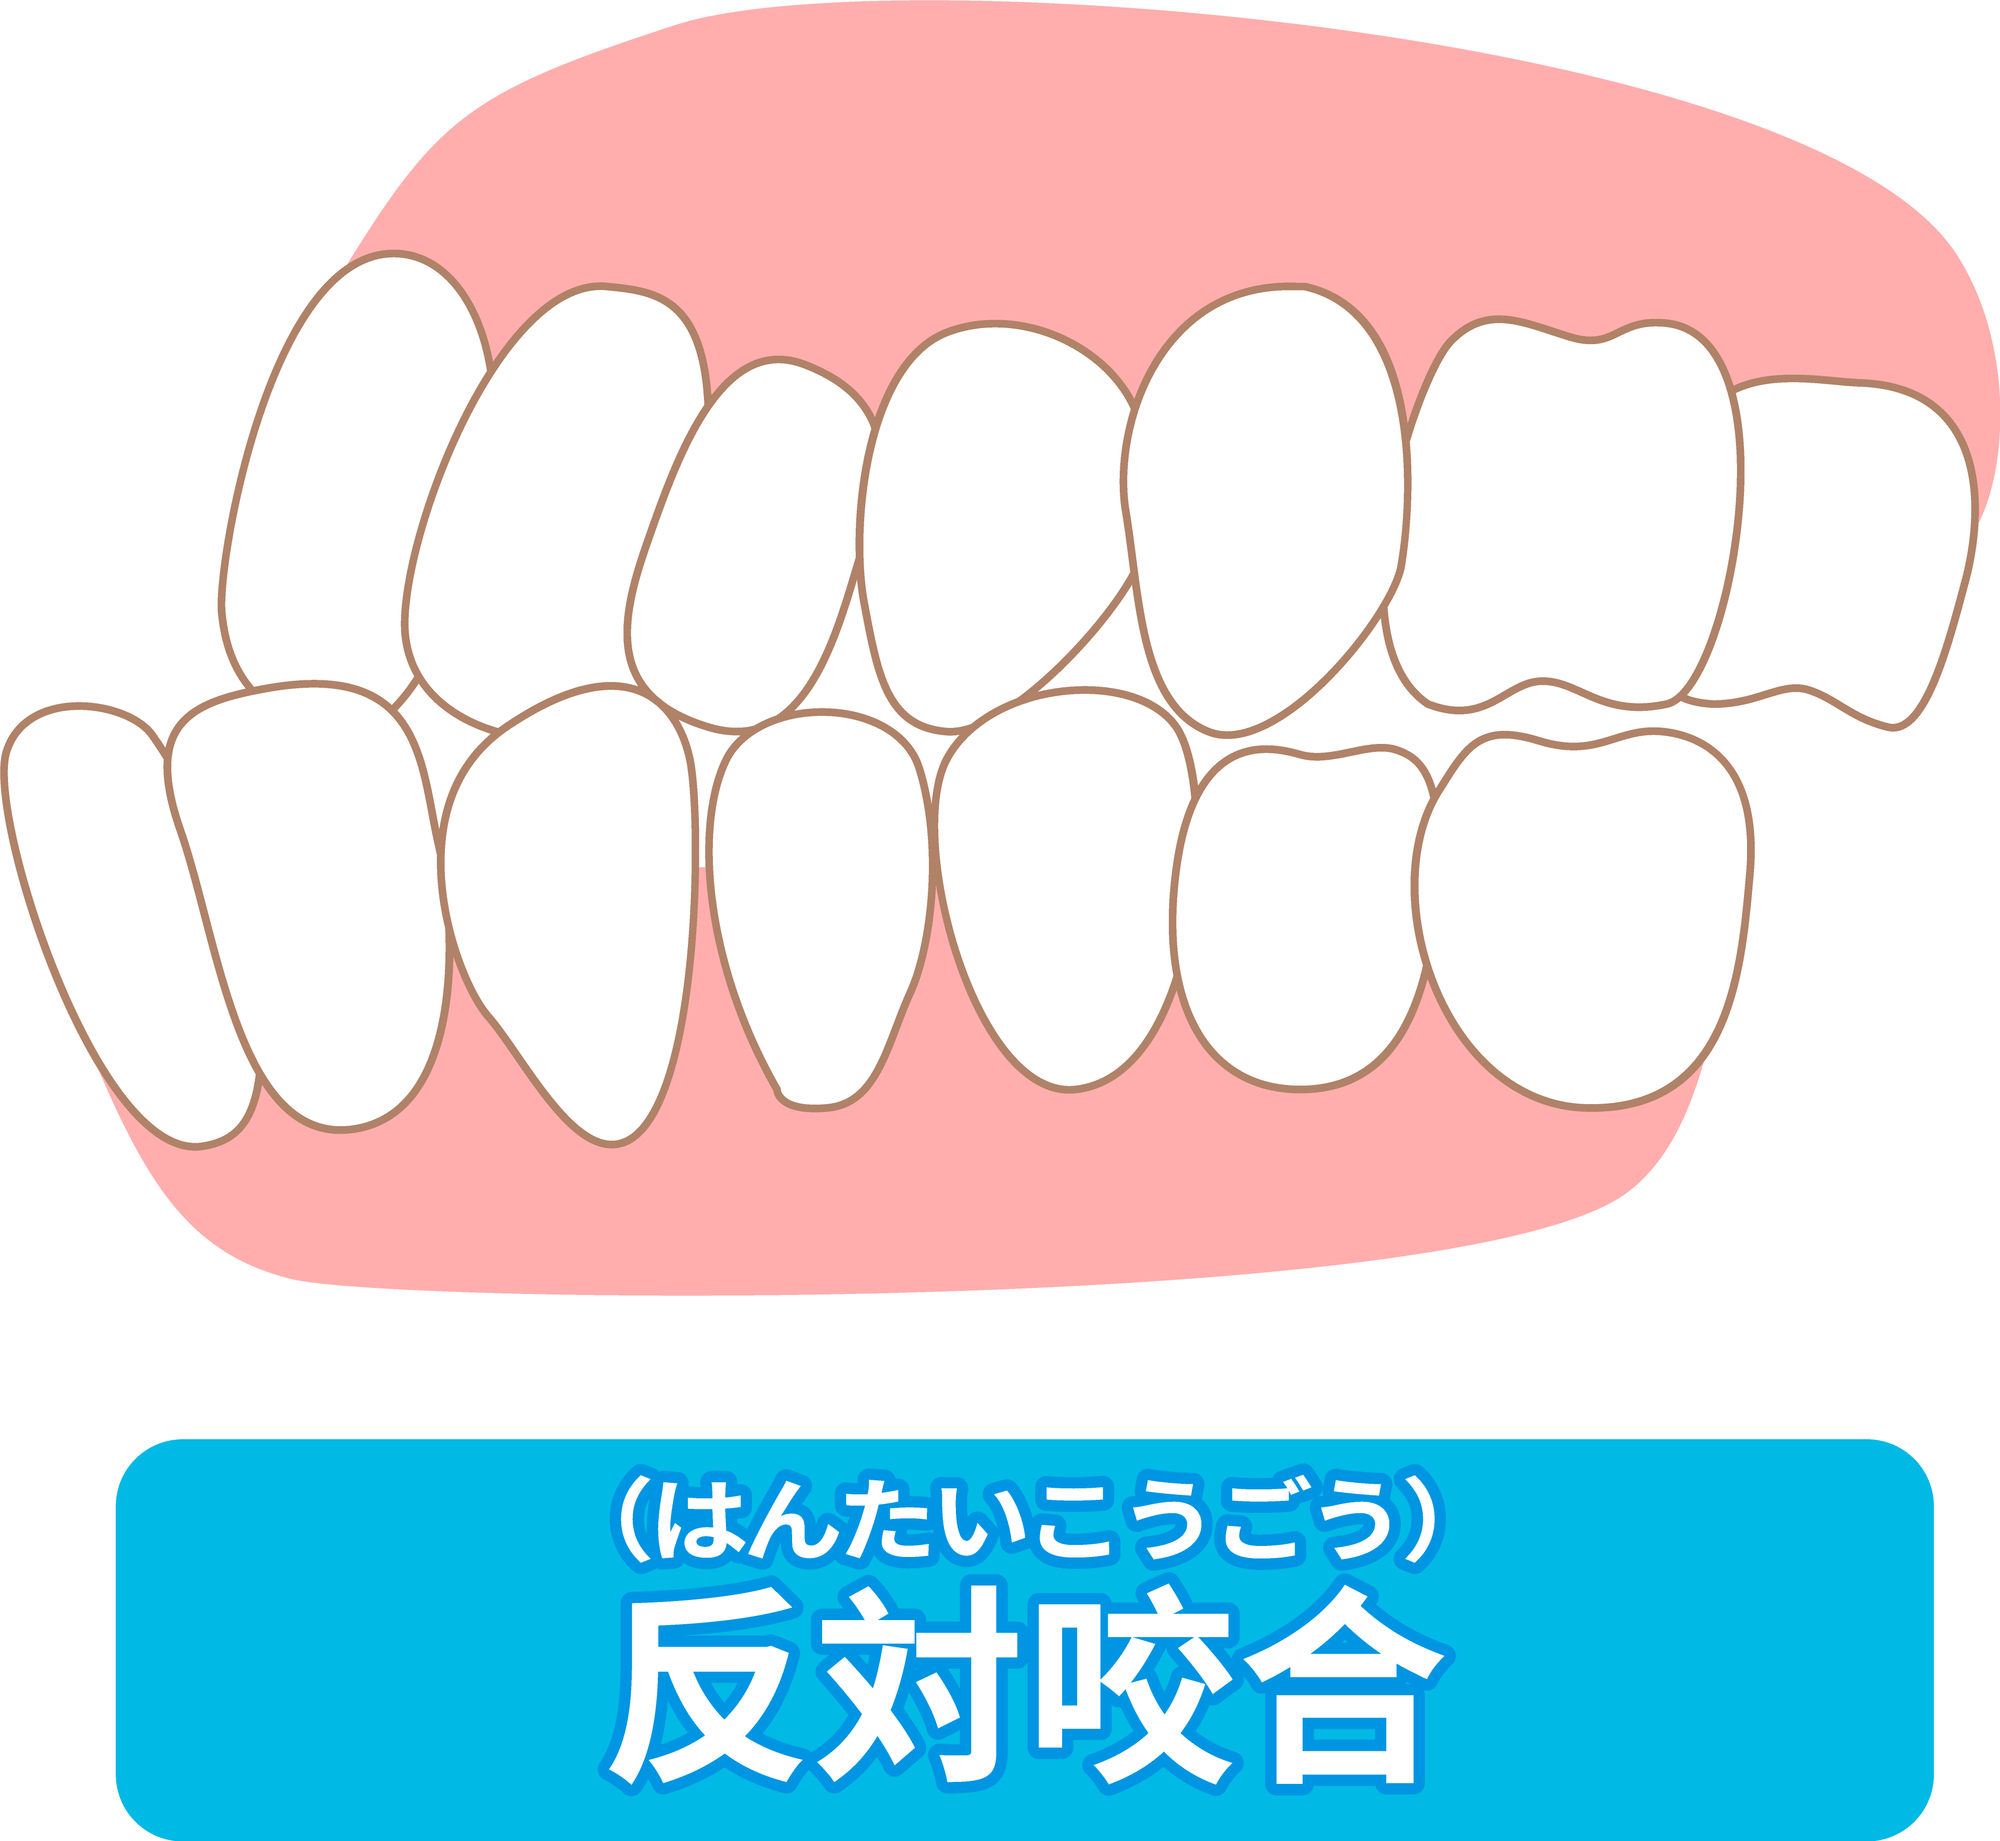

まず、受け口とは反対咬合のことをいいます。一般的には「しゃくれ」と言う事もありますね。